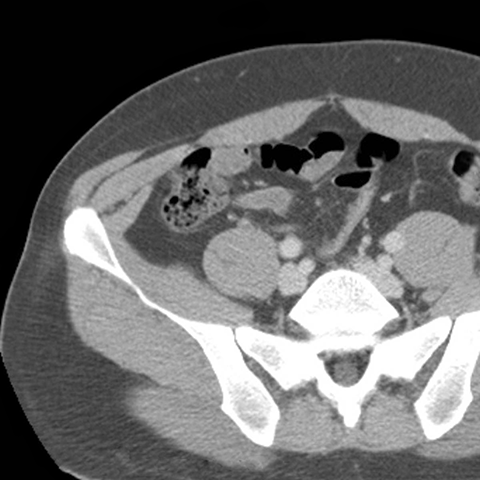

Abdominal Wall Muscles Normal Anatomy, Axial CT [6 of 9]